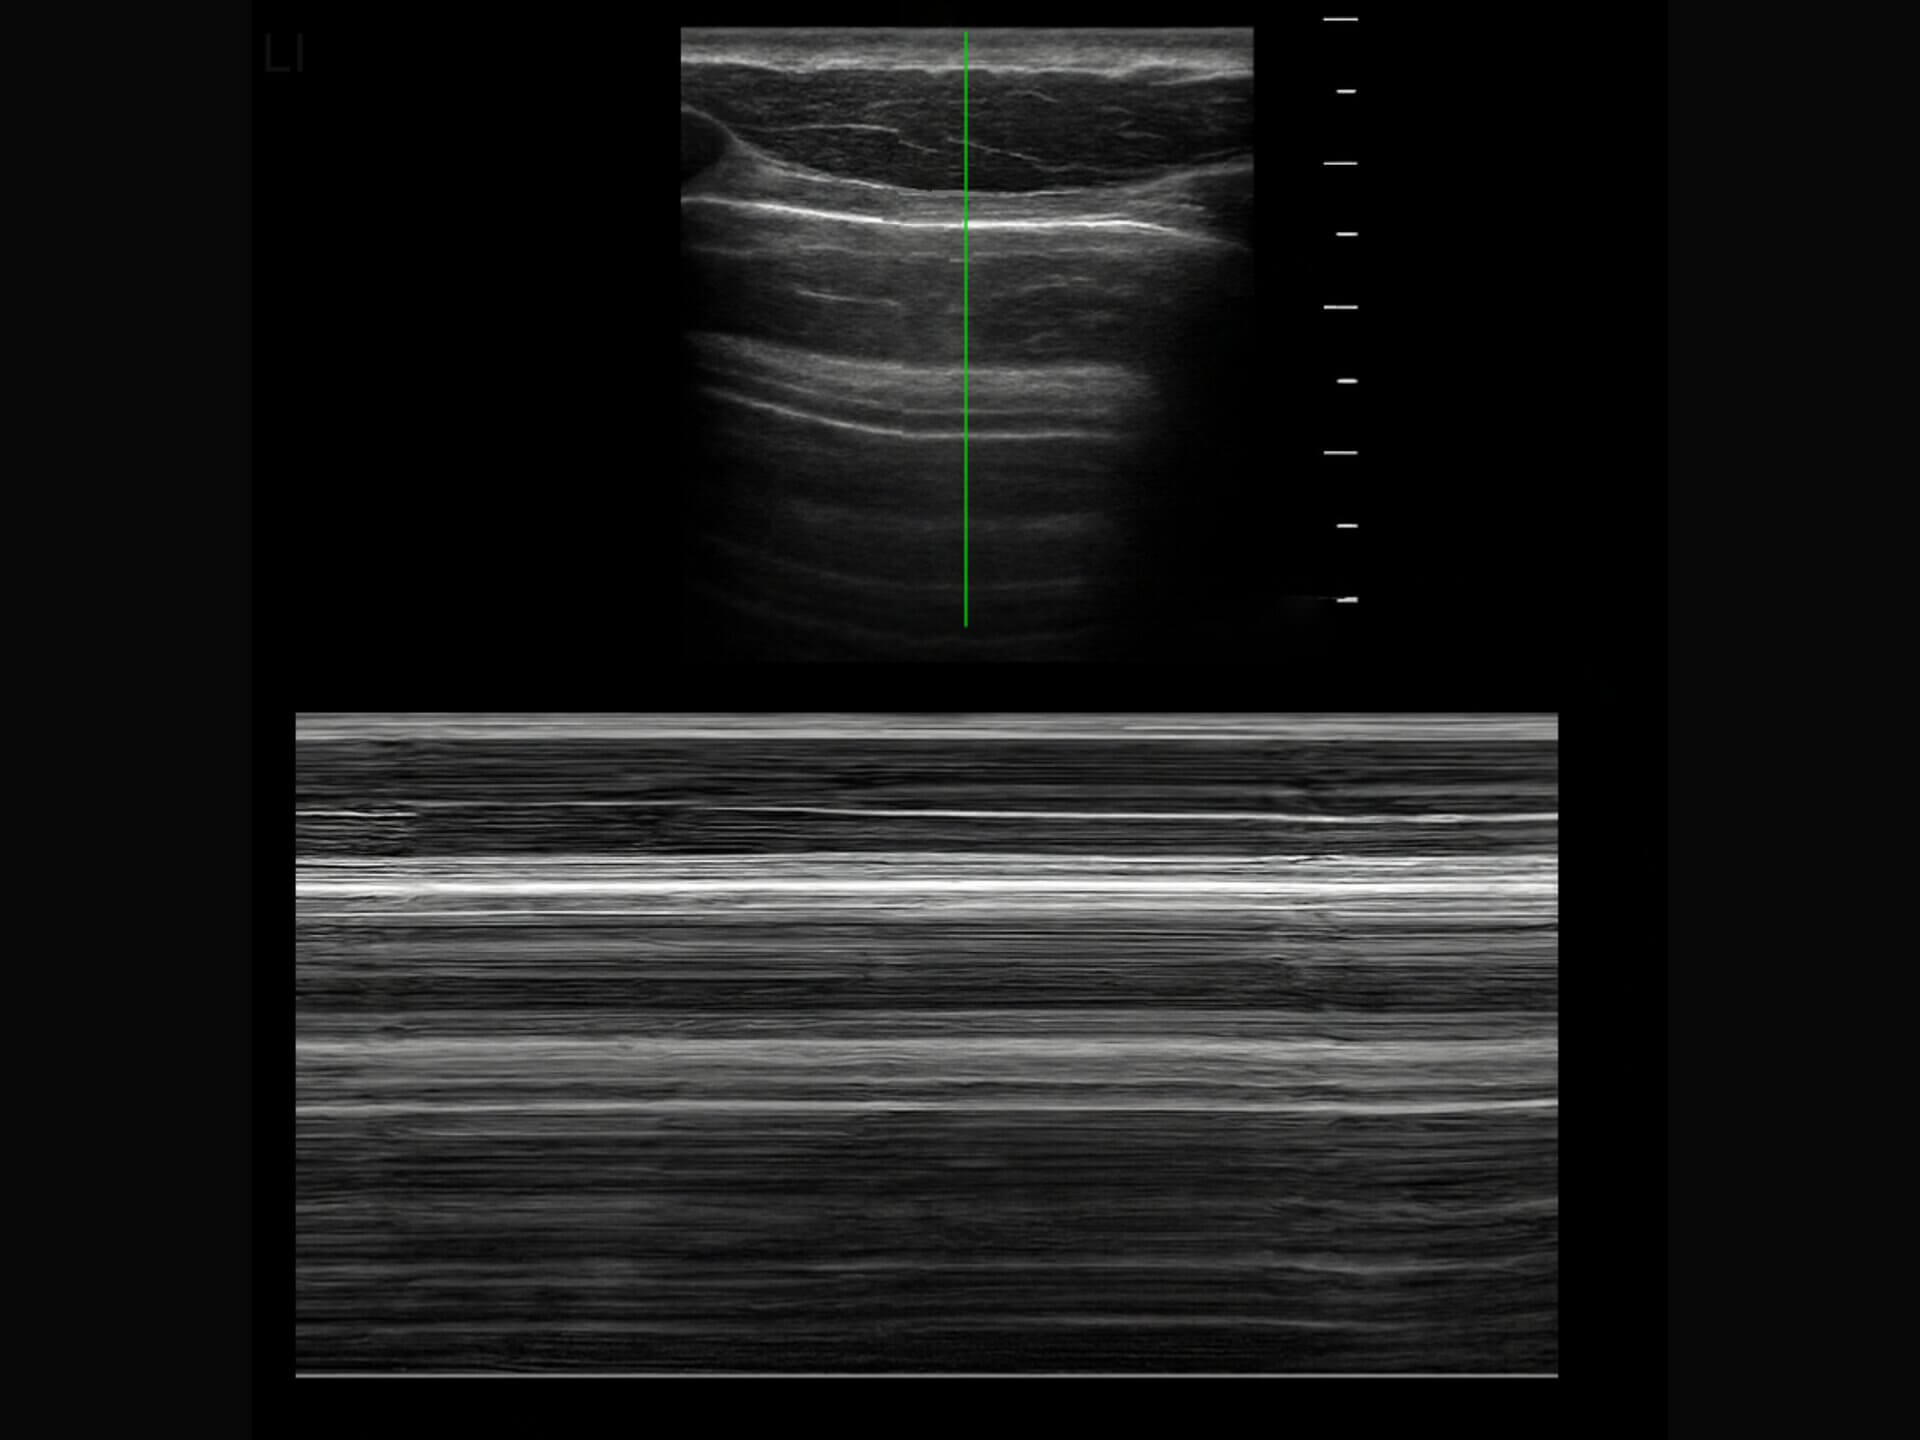

Das Barcode-Zeichen ist ein sonographisches Zeichen, das bei einem Pneumothorax im M-Mode des Lungenultraschalls sichtbar wird. Es ähnelt dem Bild eines Barcodes.

KI-generierte Darstellung, lizenziert unter CC BY-NC-SA 3.0